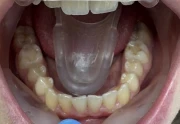

Стрипинг

Serviciul a fost efectuat la Дентално студио ТОП ДЕНТАЛ de томи пелова pe 9 Okt., 25